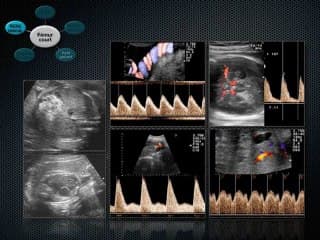

La médiathèque du Collège Français d'Échographie Fœtale (CFEF) constitue l'une des plus importantes collections de ressources vidéo dédiées à l'échographie fœtale en France. Avec plus de 3 261 vidéos, elle couvre l'ensemble des thématiques liées à la pratique échographique prénatale.

Vous y trouverez des conférences présentées lors des congrès nationaux et internationaux, des cours magistraux dispensés par des experts reconnus, des démonstrations pratiques sur des cas cliniques réels, ainsi que des podcasts et tables rondes sur les dernières avancées de la spécialité.